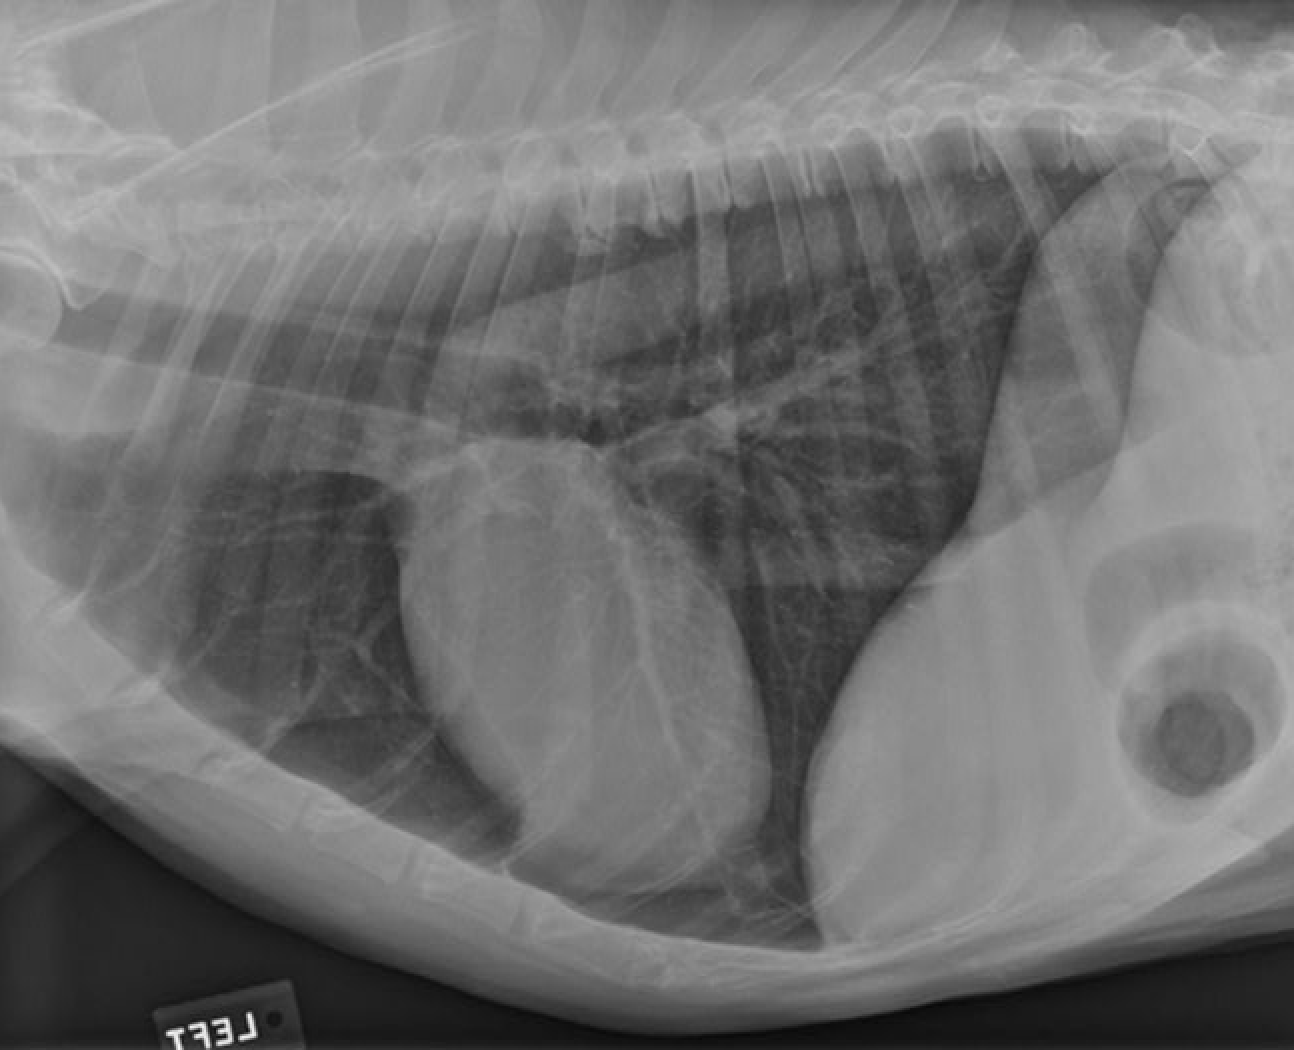

identity the structures on the thorax radiograph left lateral view

identify the right cranial lung lobe

identify the right cranial bronchus

identify the right accessory lobe of the lung

identify the right crus of the diaphragm

identify the left crus of the diaphragm

identify the dome of the diaphgram

identify the left cranial lung lobe